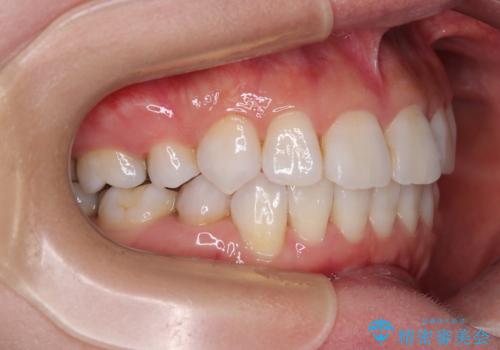

矯正治療の後戻り インビザラインで短期間矯正治療

- 上下前歯の後戻りを気にして来院された患者様です。

インビザラインでの治療を希望されていて、デコボコの程度が中等度であり、安価なパッケージにて対応可能と判断されたため、インビザライン・モデレートを用いて矯正治療を行うこととしました。

インビザライン・モデレートは、製作できるアライナーの枚数に制限があるため、移動可能な量に限りがあるものの、インビザライン・ライトよりも枚数が多いため、幅広い症例に対応可能です。